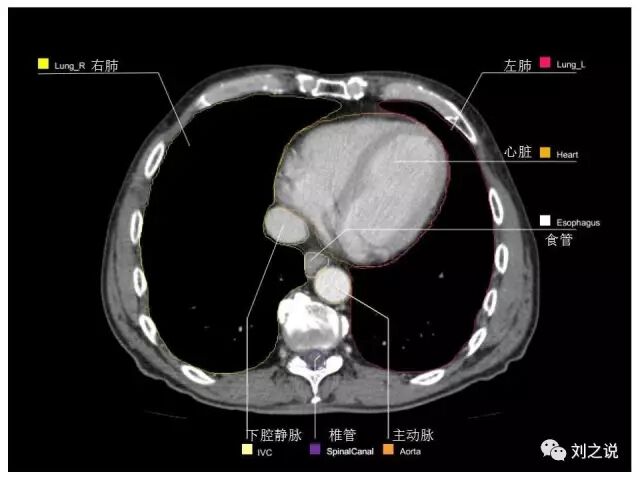

参考RTOG共识和3D-body解剖。

来源:刘之说